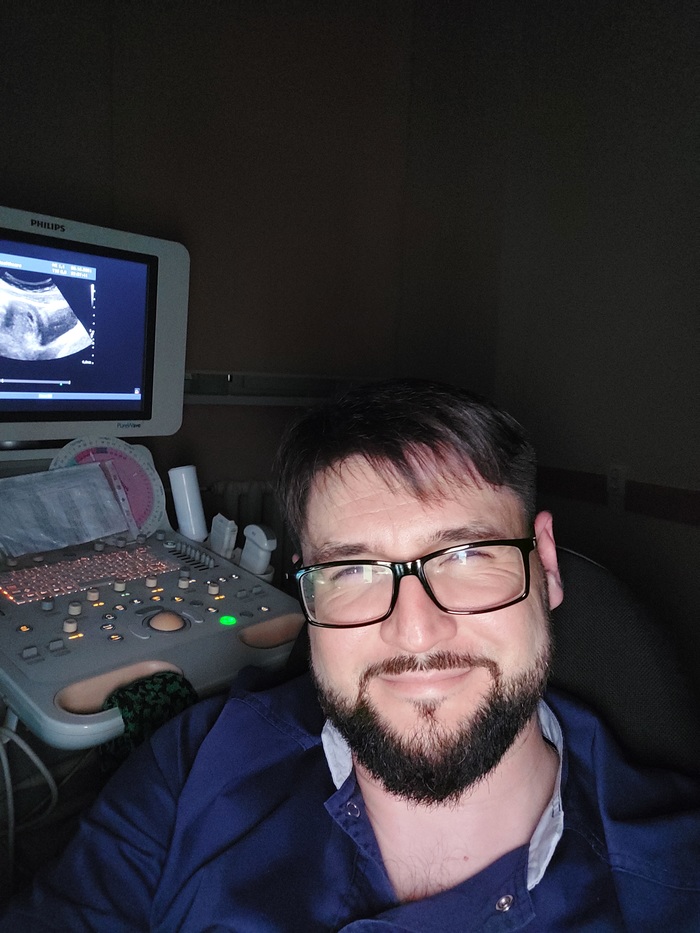

Продержали под капельницей до понедельника и с направлением отправили в другой город. 3 часа на такси, чуть не потерял сознание. Экстренно приняли в хирургию, сделали УЗИ. Камень 9 мм.

Либо он за неделю вырос в три раза, либо узист тоже разглядывал кроликов на мониторе за мои деньги.